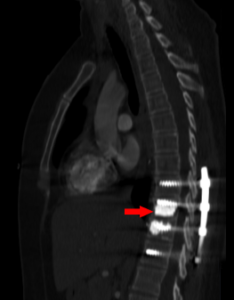

CT sagital bone window.